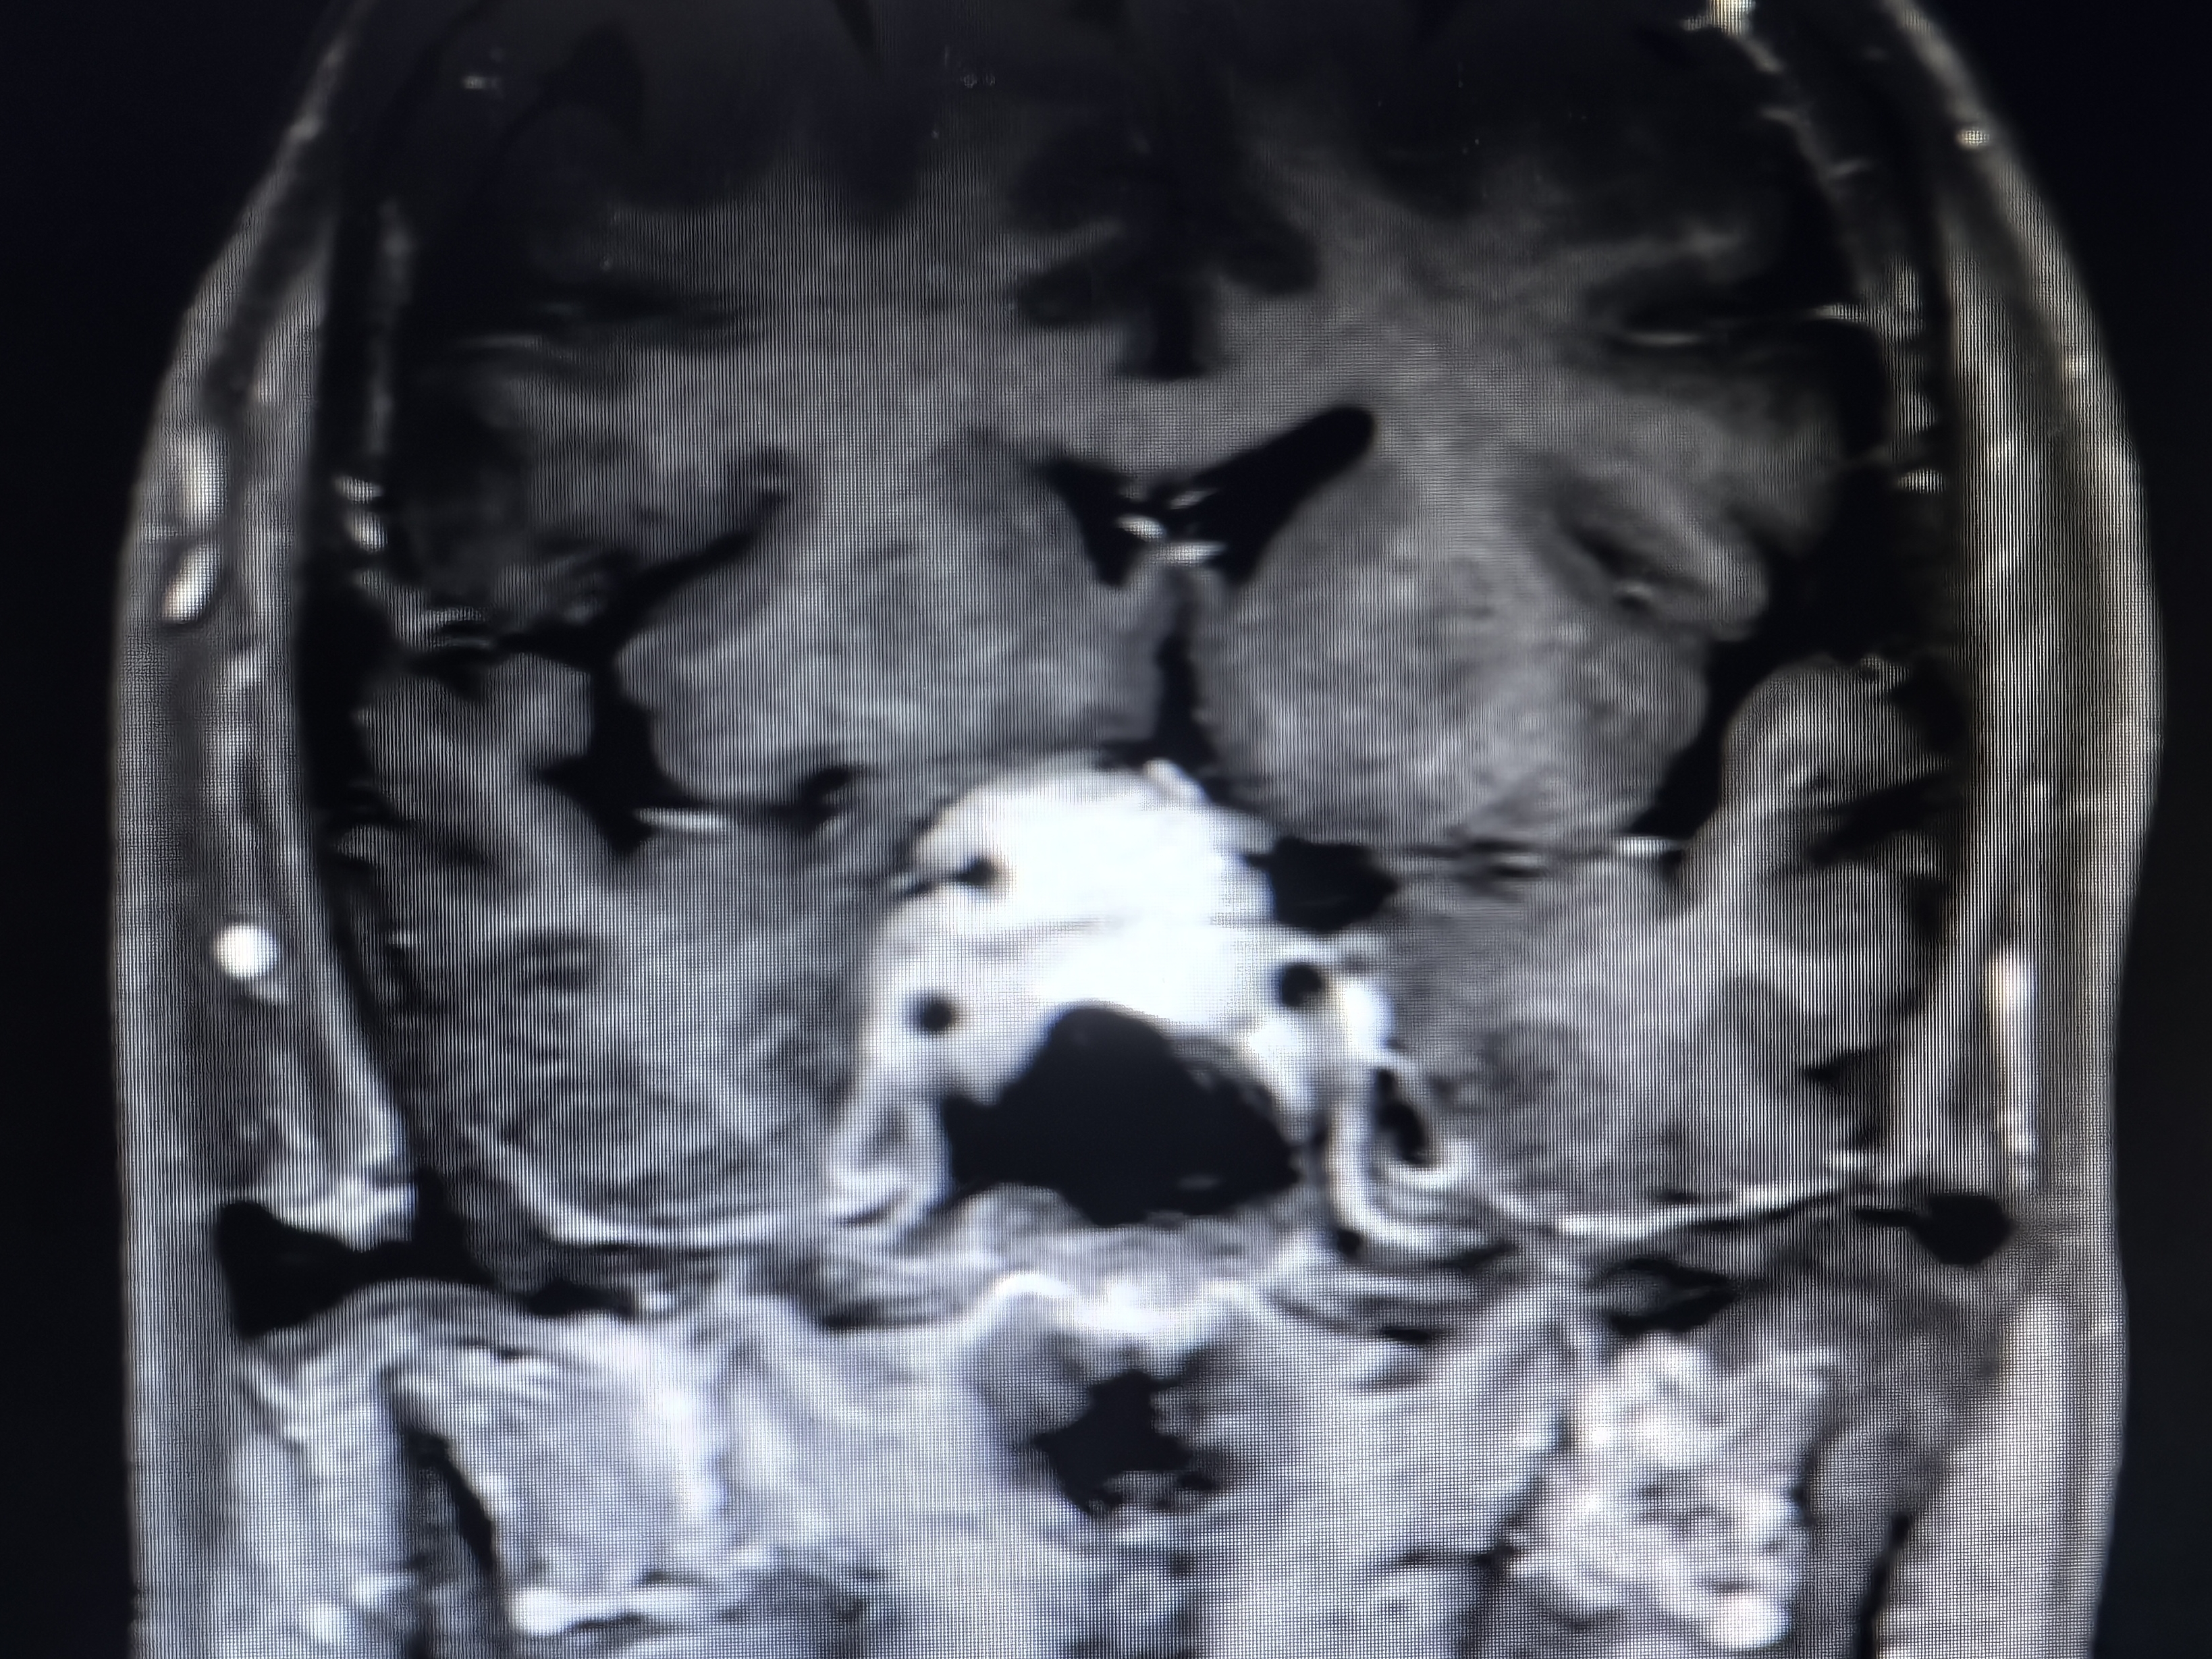

下面展示本病房几例病例:

病例二